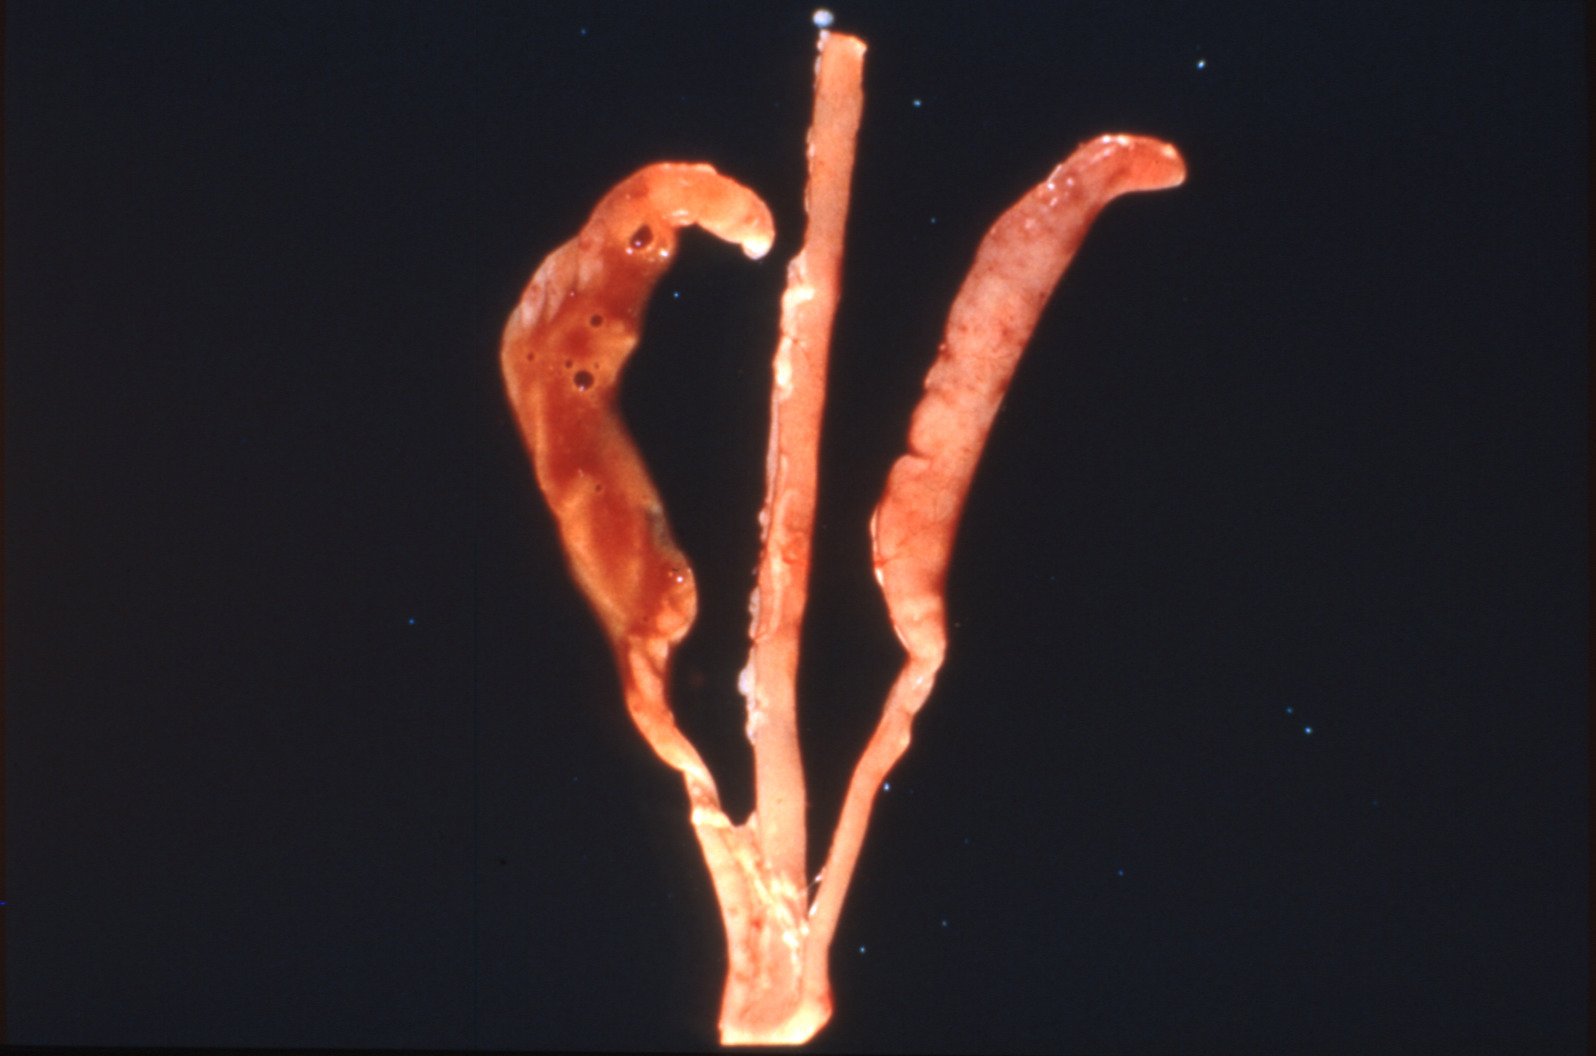

Coccidiosis in chickens and turkeys (slide study set no. 7)

Avian coccidiosis Avian medicine Chickens--Diseases Turkeys--Diseases